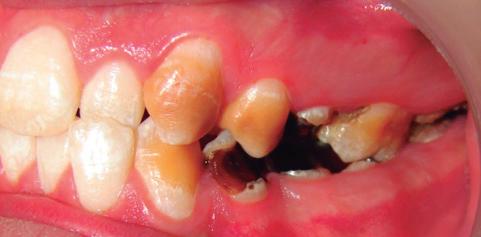

Este manual proporciona información completa y actualizada para profesionales de la odontología acerca de la amelogénesis imperfecta, una enfermedad huérfana que se caracteriza por desórdenes hereditarios que afectan la estructura del esmalte en su calidad y cantidad. Esta patología muchas veces se subdiagnostica en la práctica general, por lo que este manual suministrará una guía que permitirá un diagnóstico certero; además, brindará una clara y comprensible explicación a otros profesionales de la salud, como médicos y nutricionistas, que podrían interactuar con pacientes afectados por esta enfermedad, ya que esta entidad se ha asociado también a factores nutricionales y a enfermedades sistémicas.

A pesar de los recientes avances en la identificación de los defectos moleculares responsables de la aparición de la amelogénesis imperfecta, existe poca información sobre el fenotipo y el genotipo de este

grupo de desórdenes, lo que dificulta el diagnóstico de algunos subtipos clínicos y, por lo tanto, la determinación del programa terapéutico. Describir las características dentales y craneofaciales, así como otras enfermedades asociadas que pueden estar relacionadas con pacientes que padecen amelogénesis imperfecta, proporciona elementos para una adecuada planeación de su tratamiento. La intervención de varios profesionales para remediar los múltiples y severos problemas funcionales y estéticos presentes en esta enfermedad se hace necesaria, así como conocer su etiología genética, con el fin de brindar al paciente una atención integral.